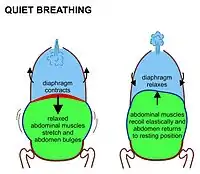

The lungs are not capable of inflating themselves, and will expand only when there is an increase in the volume of the thoracic cavity.[6][7] In humans, as in the other mammals, this is achieved primarily through the contraction of the diaphragm, but also by the contraction of the intercostal muscles which pull the rib cage upwards and outwards as shown in the diagrams on the right.[8] During forceful inhalation (Figure on the right) the accessory muscles of inhalation, which connect the ribs and sternum to the cervical vertebrae and base of the skull, in many cases through an intermediary attachment to the clavicles, exaggerate the pump handle and bucket handle movements (see illustrations on the left), bringing about a greater change in the volume of the chest cavity.[8] During exhalation (breathing out), at rest, all the muscles of inhalation relax, returning the chest and abdomen to a position called the "resting position", which is determined by their anatomical elasticity.[8] At this point the lungs contain the functional residual capacity of air, which, in the adult human, has a volume of about 2.5–3.0 liters.[8]

Diaphragmatic breathing causes the abdomen to rhythmically bulge out and fall back. It is, therefore, often referred to as "abdominal breathing". These terms are often used interchangeably because they describe the same action.